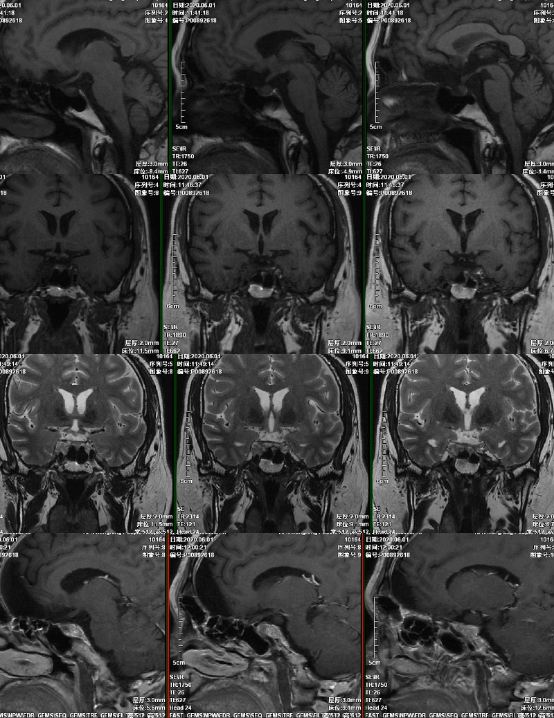

术后复查磁共振

术后磁共振

6月后复查磁共振